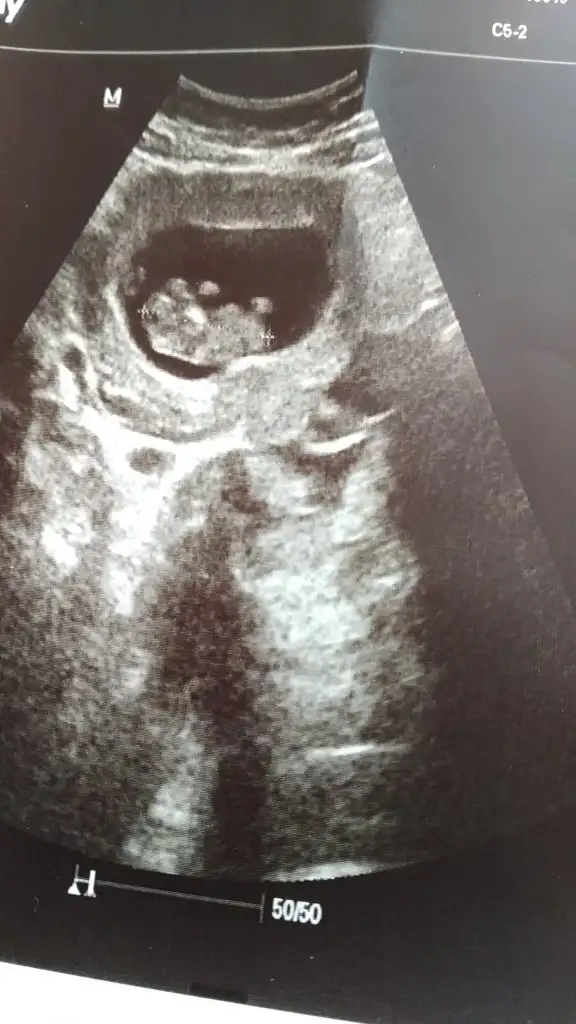

Nub için 11 12 13 haftalar olmalı sanki kız gibi emin olamadımBana da bakabilir misin nub teorisi için belli oluyorsa ben hiç anlamıyorum da

10+3 fotosuydu bu. Çok teşekkür ederim tahmin için gönlümdekini söyledin valla sevindim yinedeNub için 11 12 13 haftalar olmalı sanki kız gibi emin olamadım